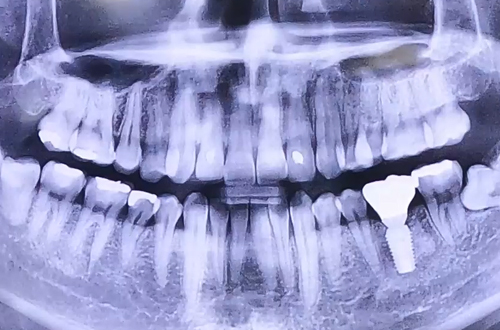

AFTER

치료 유형 뼈이식 임플란트